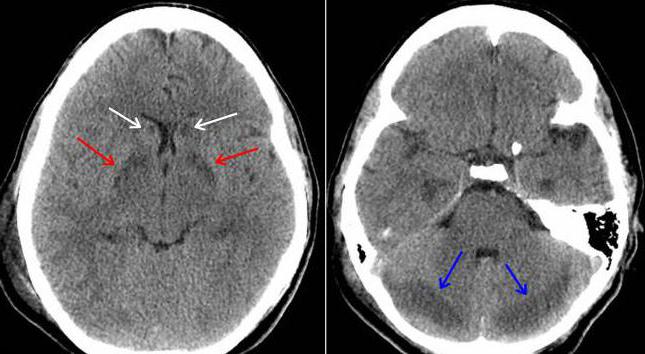

• отек головного мозга;

При легких и средних степенях тяжести отравления пациента долгое время могут беспокоить головные боли, головокружение, снижение памяти и интеллекта, эмоциональная нестабильность, что связано с поражением серого и белого вещества головного мозга.

• кожно-трофические расстройства (отеки с последующим некрозом тканей);

• субарахноидальные кровоизлияния;

• нарушение мозговой гемодинамики;

• отек мозга;

• полиневриты;

• нарушение зрения и слуха до полной потери;

• инфаркт миокарда;

• тяжелые пневмонии, осложняющие кому.